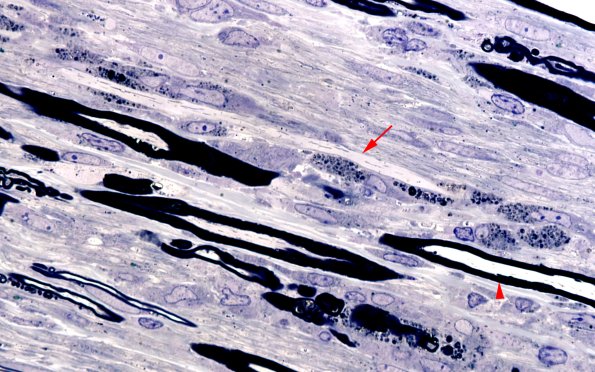

A longitudinal section shows a demyelinated axon with clusters of myelin-debris containing macrophages along its surface. Compare the nearby axon with a normal myelin sheath (arrowhead). (Plastic section)